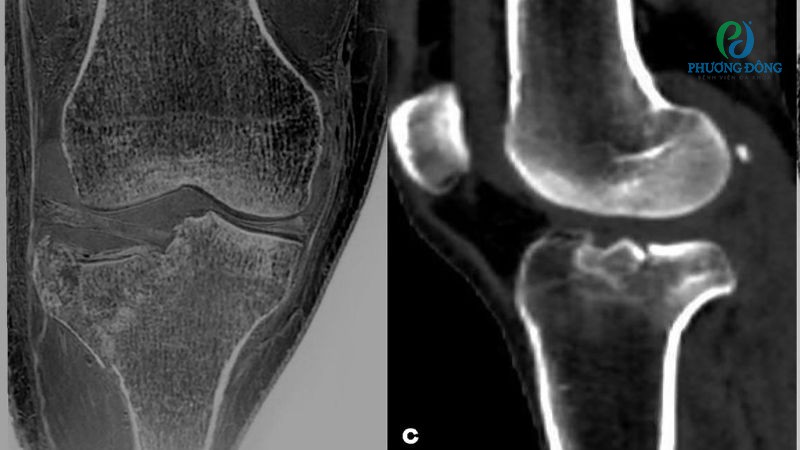

Rách, đứt dây chằng khớp gối

Dây chằng là các dải mô đàn hồi kết nối xương, duy trì sự ổn định và sức mạnh cho các khớp. Khớp gối là bộ phận dễ chịu lực tác động dẫn đến rách, đứt, tùy trường hợp có thể xảy ra ở dây chằng chéo trước, dây chằng chéo sau, dây chằng bên trong hoặc dây chằng bên ngoài.

Rách sụn chêm

Rách sụn chêm cũng thường xảy ra khi thực hiện các chuyển động gập, vặn hoặc xoay mạnh đầu gối. Chấn thương này đặc biệt phổ biến ở vận động viên, người thường xuyên chơi thể thao đối kháng như bóng đá, bóng rổ, bóng chuyển hoặc cầu lông.

- Siêu âm phù hợp với những trường hợp cần đánh giá cấu trúc phần mềm như gân, cơ, dây chằng, gợi ý dấu hiệu nhiễm trùng trong và ngoài khớp.

- Chụp CT-Scan giúp đánh giá tổn thương trên không gian 3D, hỗ trợ quan sát các vấn đề liên quan đến xương, cơ, mỡ và các cơ quan khác.

- Chụp MRI cung cấp hình ảnh chi tiết, sắc nét về các cấu trúc mô mềm, khoang tủy xương và khối u xương.